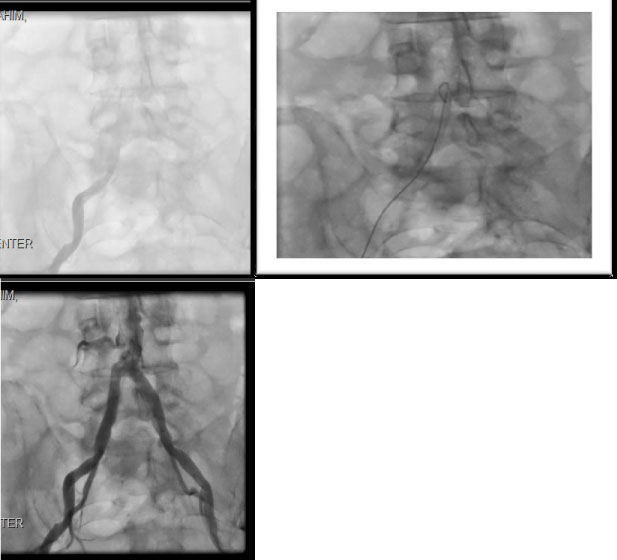

The patient underwent peripheral, coronary/grafts, and carotid angiography after obtaining high risk consent. Lower extremities angiography was done first showed bilateral iliac occlusion and underwent successful bilateral iliac angioplasty and stenting (as he was deemed not a surgical candidate) with balloon expandable 10 × 59 mm stents with excellent patency and flow (Figures 2).

Figure 2: Showing bilateral iliac calcific occlusion (pre) and post Iliac Artery Stents Bilaterally. View Figure 2